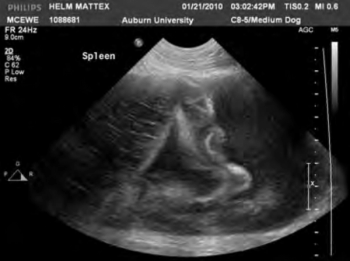

Radiography is an integral diagnostic tool in companion animal practice. Here are brief guidelines for obtaining the most useful images of the abdomen in dogs and cats.